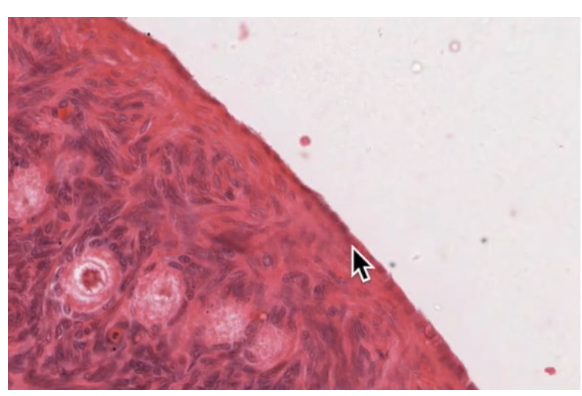

Palatine tonsil

Guard the opening to the gastrointestinal and respiratory systems

Luminal surface = SS projecting deep into tonsil forming crypts

Crypts lined with lymphoid tissue and lympoid nodules